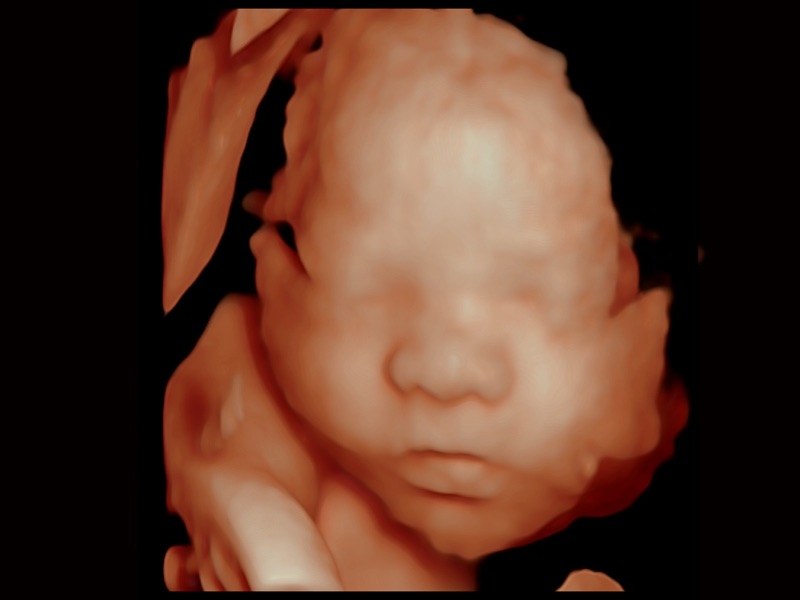

三維光影成像技術(shù)采用新型的渲染方式,增強(qiáng)邊緣信息,使得輪顯示清晰完整,為臨床提供豐富、直觀的三維結(jié)構(gòu),提供臨床診斷準(zhǔn)確性。